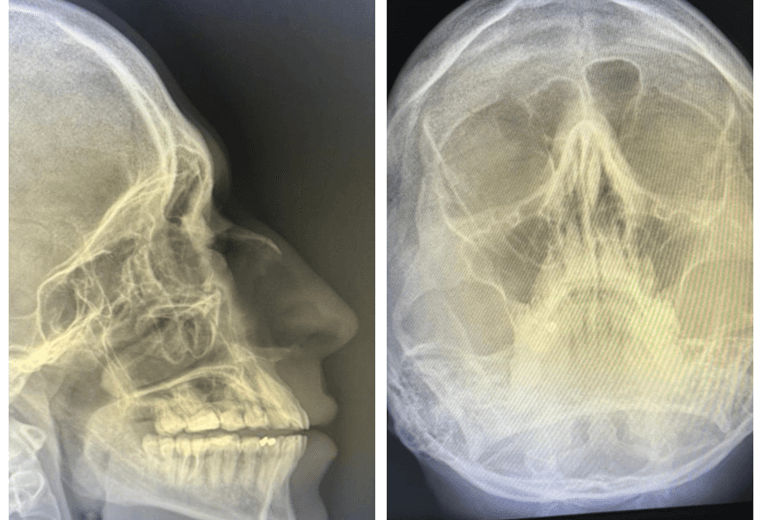

Pese a que las placas de rayos X del coreógrafo Javier Acuña confirman que tiene una fractura en su nariz, eso no lo detendrá. Pese a la lesión, él y Lisbeth Valverde bailarán esta noche en la gala de "Mira quién baila".

Las radiografías confirmaron una desviación del tabique nasal; sin embargo, la lesión no amerita operación porque no resultó tan grave.

Durante este domingo, Acuña ha estado con analgésicos para desinflamar y le harán una "reducción", el cual es un procedimiento que consiste en volver a alinear los huesos de la nariz que se han desplazado.